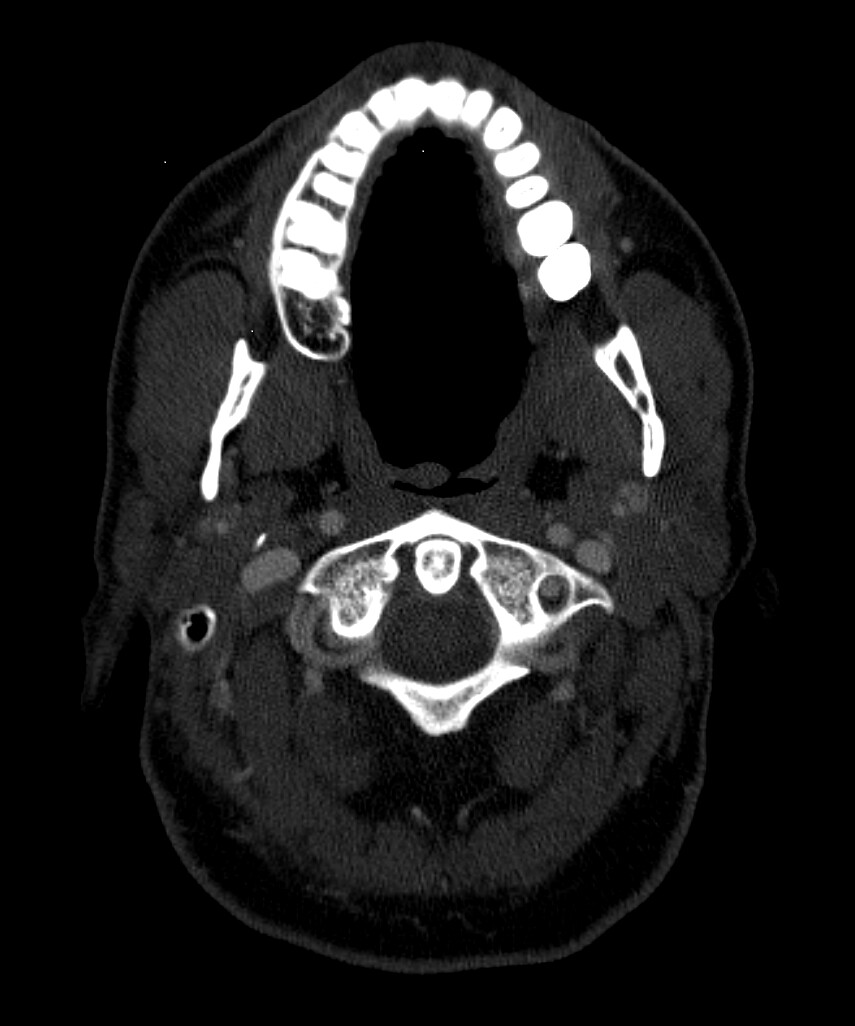

I did have an MRA done at Mayo that showed severe blood flow compression on my left side with my arms up. Because of this test, I went back to UCLA and did tests for Thoracic Outlet Syndrome. The limited tests they can do for this seemed to help. So, I had a left rib resection 2 yrs ago. Before this surgery, I did do a CT w/wo contract to look for Eagles and the report came back saying my stylohyoid was normal. So I went ahead with the thoracic outlet surgery. That surgery got rid of the daily headache I was dealing with. It seemed to have relieved pressure headaches and some of the loss of feeling in my arm. It never helped with the facial pains and dizziness though that I live with. Months after this surgery, I also developed Frozen Shoulder. I found it odd I got this so long after the surgery and when I was in PT. It seemed like the more we tried to use my arm and mess with my neck, the worse it got. I then went back to Mayo and had a head and face MRI that showed compression of my vagus nerve with an artery around my brainstem. It also showed a blood vessel touching my trigeminal nerve which is what they look for with trigeminal neuralgia surgery. So I took this and followed this lead. After visiting three trigeminal neuralgia surgeons, most of them said since I didn’t live with shooting lightning pains, I wasn’t a good candidate for the surgery. I was referred to some neurosurgeons regarding the vagus nerve compression at the brain stem. I almost had surgery booked for this and then the dr said something more is going on here, let’s hold off. This led me to circle back to Eagles Syndrome. Even though my CT hadn’t shown eagles on the report, I took it to Dr. Osborne. He indicated I had a calcified ligament. I almost moved forward with surgery, but I am concerned about the vascular issues I know I’m experiencing. I worry that I need to ensure we target these issues in my surgery. In the past few years, I’ve had near fainting spells, dizziness (I no longer can drive), BP issues that were similar to POTS but not, heart palpitations, horrible brain fog, and a complete inability to concentrate. I also get left sided body numbness and weakness. My left leg can even be impacted. It’s not to where I can’t walk but it feels like I’m living on a cruise ship trying to balance myself and my left side is weak. I feel like I need to confirm I have vascular issues and make sure I care for this in surgery. I tried to get a second opinion with an ENT at UCLA and they said they saw nothing wrong with my stylohyoid but that they see something wrong with my hyoid bone that they might be willing to operate on.

I really need help reading my images myself. I have anonymized them, but I don’t even know how to provide the right image to view here. I want to be able to advocate well for myself but I need to know what I’m looking at. I feel like the group on here know more than any doctors at this point. I would love to get back to normalcy…driving my kids around, actually getting sleep, being able to think clearly, being able to physically exercise, to be thriving and not barely surviving. Things I took for granted before this, I won’t again. Pls help if you are able. I can post my images following this first post though guidance on steps would be appreciated.